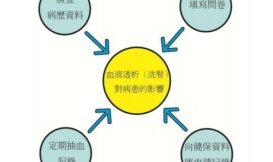

在前篇關於健保資料庫的簡介裡,有提到研究者可以依其需求,串連散布在健保資料庫內不同檔案間的資料。而有些研究,不僅使用健保資料庫的資料,也可能串連其他非健康類資料庫,甚至相同的研究方法也可以適用在除了健保資料庫以外,任何資料庫間的交叉比對,而這個部分要介紹的,即為以申請不同資料庫資料,與在其間串連的「健康資料加值應用」。